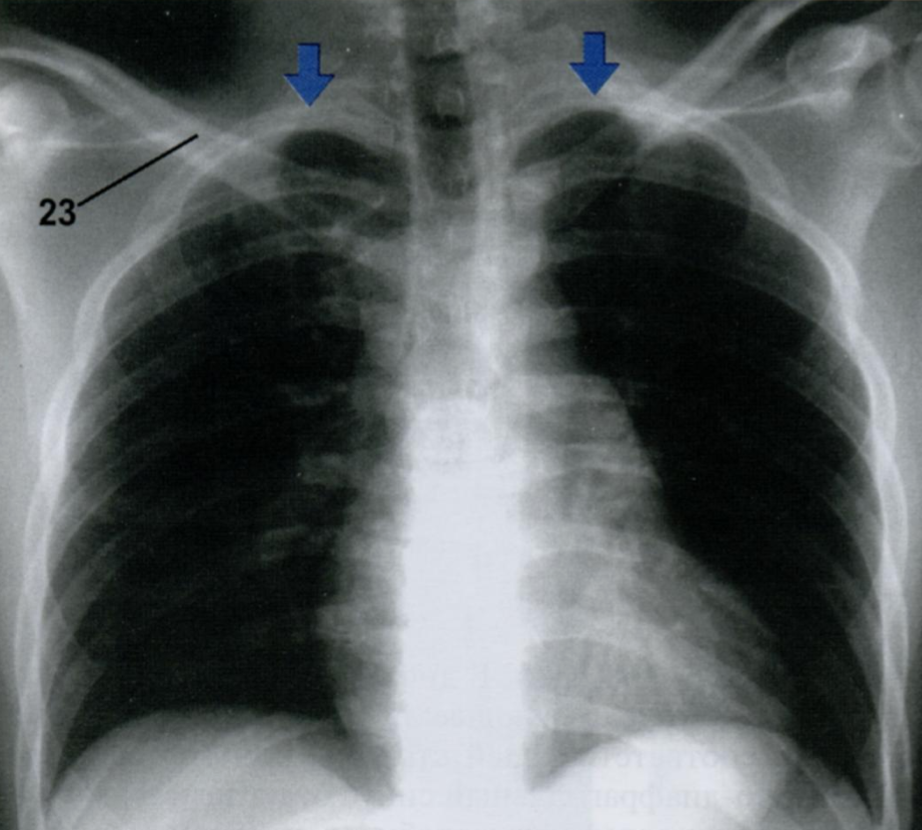

Rx лежа и на выдохе (обратите внимание на положение верхушек легких, отмечены стрелками)

Если мы выполним Rx органов грудной клетки на выдохе, то из-за высокого стояния куполов диафрагмы, сердце будет казаться приподнятым и расширенным, а сосуды легких сдавлены и полнокровны.